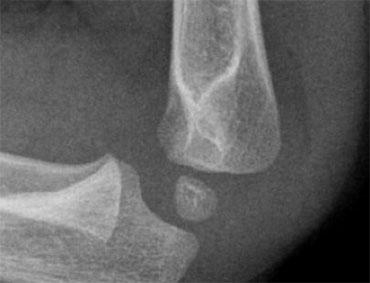

Supracondylar fractures. In A the anterior humeral line passes through the anterior third of the capitellum and in B even more anteriorly. Notice positive posterior fat pad sign in both cases

Gãy xương trên lồi cầu (2)

Nếu chỉ có di lệch tối thiểu hoặc không có di lệch, các gãy xương này có thể ẩn trên phim X-quang.

Dấu hiệu duy nhất sẽ là dấu hiệu đệm mỡ dương tính.

Thường có một số di lệch và đường cánh tay trước sẽ không đi qua trung tâm của chỏm con mà đi qua một phần ba trước hoặc thậm chí phía trước chỏm con (hình).